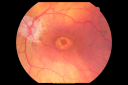

Best Disease - Left Eye Treated Previously, Elsewhere, with PDT and Avastin949 views11-year-old has Best’s disease that runs in his family on his mothers side. At another retina specialists office, he had photodynamic laser in April of 2009 and Avastin subsequently in June of 2009. Unfortunately with that his vision is substantially declining. OD 20/30, OS 20/100